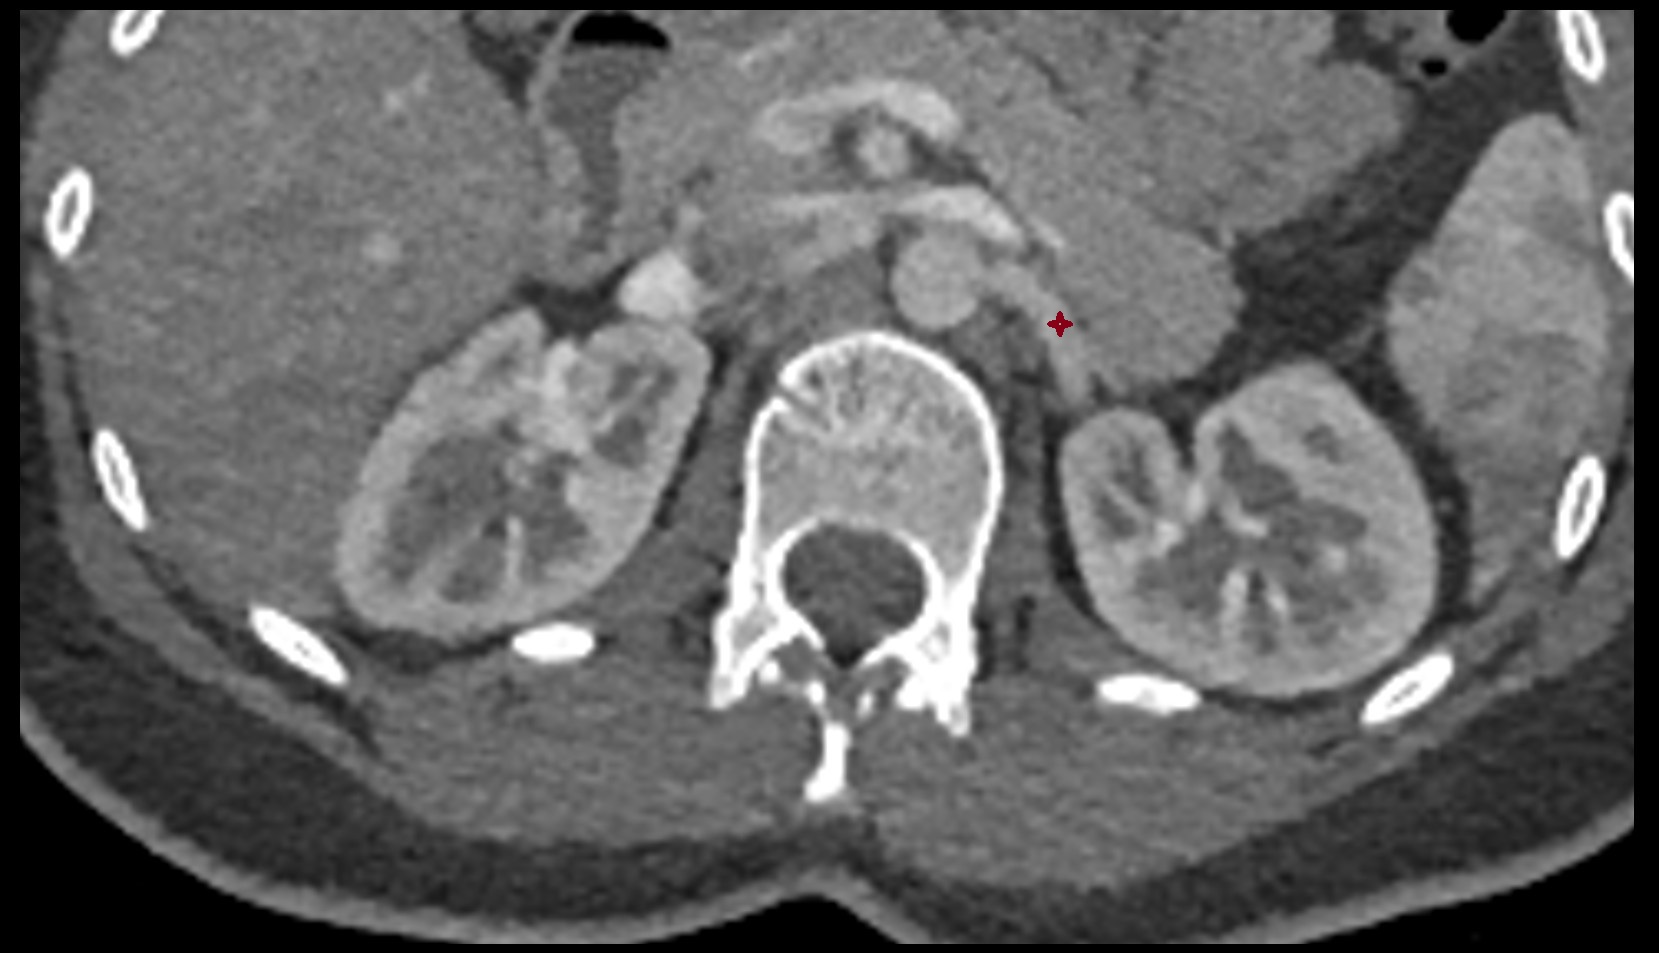

- kidneys

- Right kidney

- Left kidney

- Kidney cortex (Renal cortex)

- Renal medulla

- Renal pyramids

- Adrenal gland

- Ureters

- Renal artery

- Renal vein